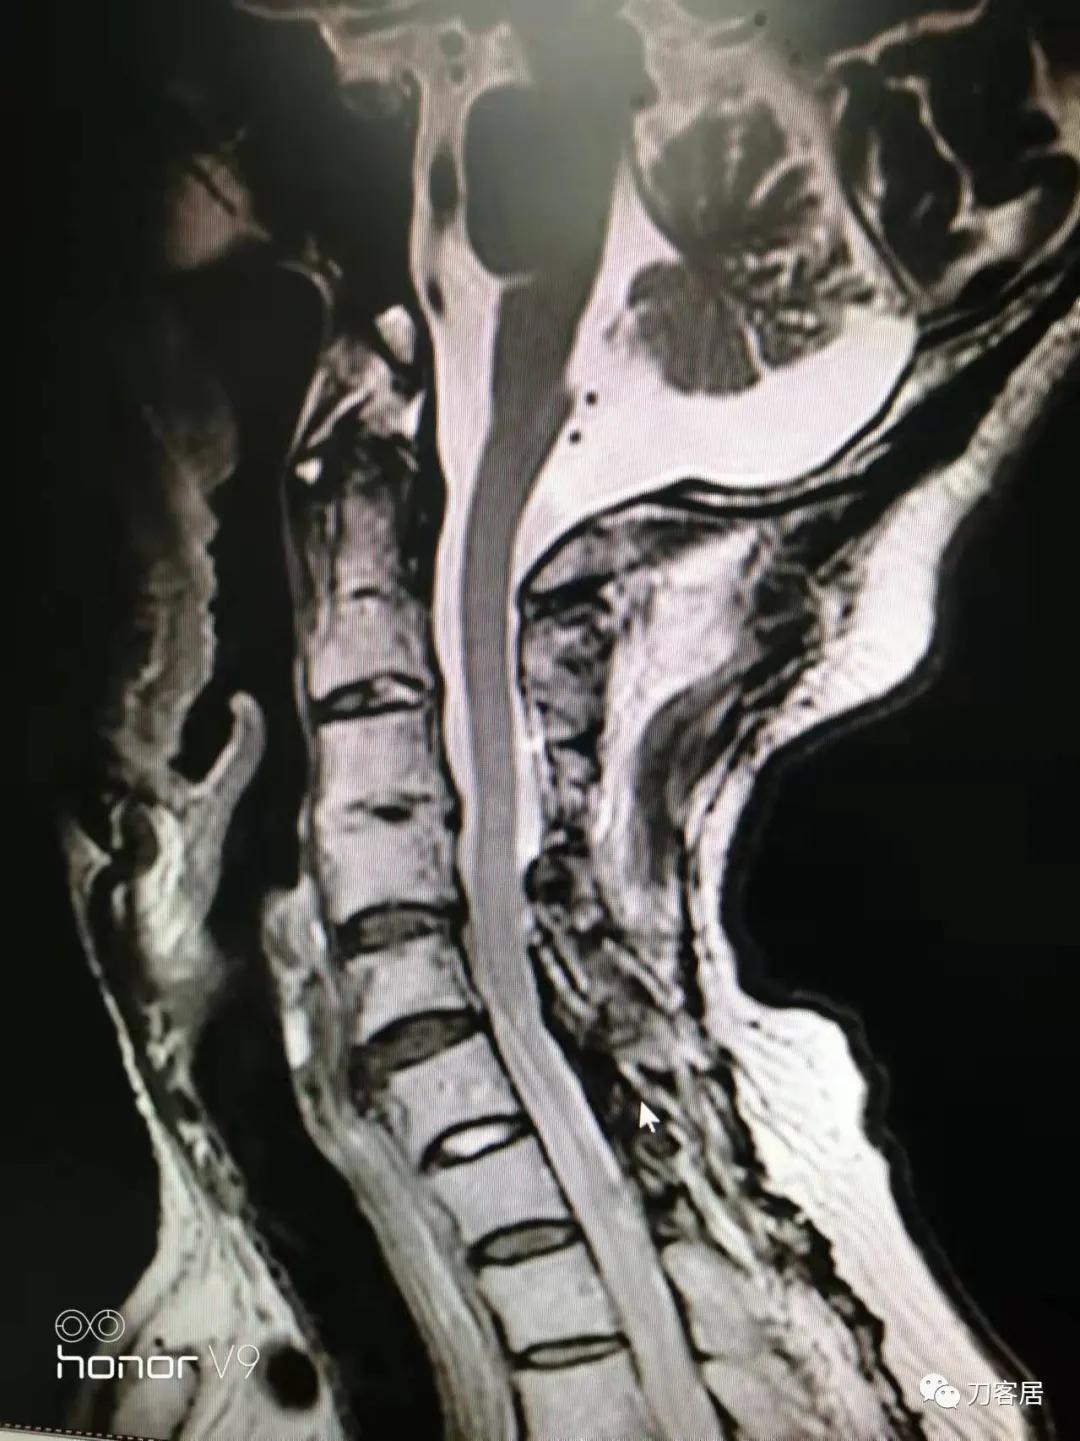

图22. 颈椎MRI-日期不明-应该是近期复查片1

从这两张颈椎MRI片子来看,颈3-4椎体分节不全,颈2-5椎管成形手术减压很好,椎管无狭窄,脊髓后移,颈5-7椎管有狭窄,脊髓信号改变。此信号改变可能系脊髓萎缩,也可能是头段脊髓后移后,颈5-6节段后方椎板仍在,椎管相对狭窄,脊髓受压。